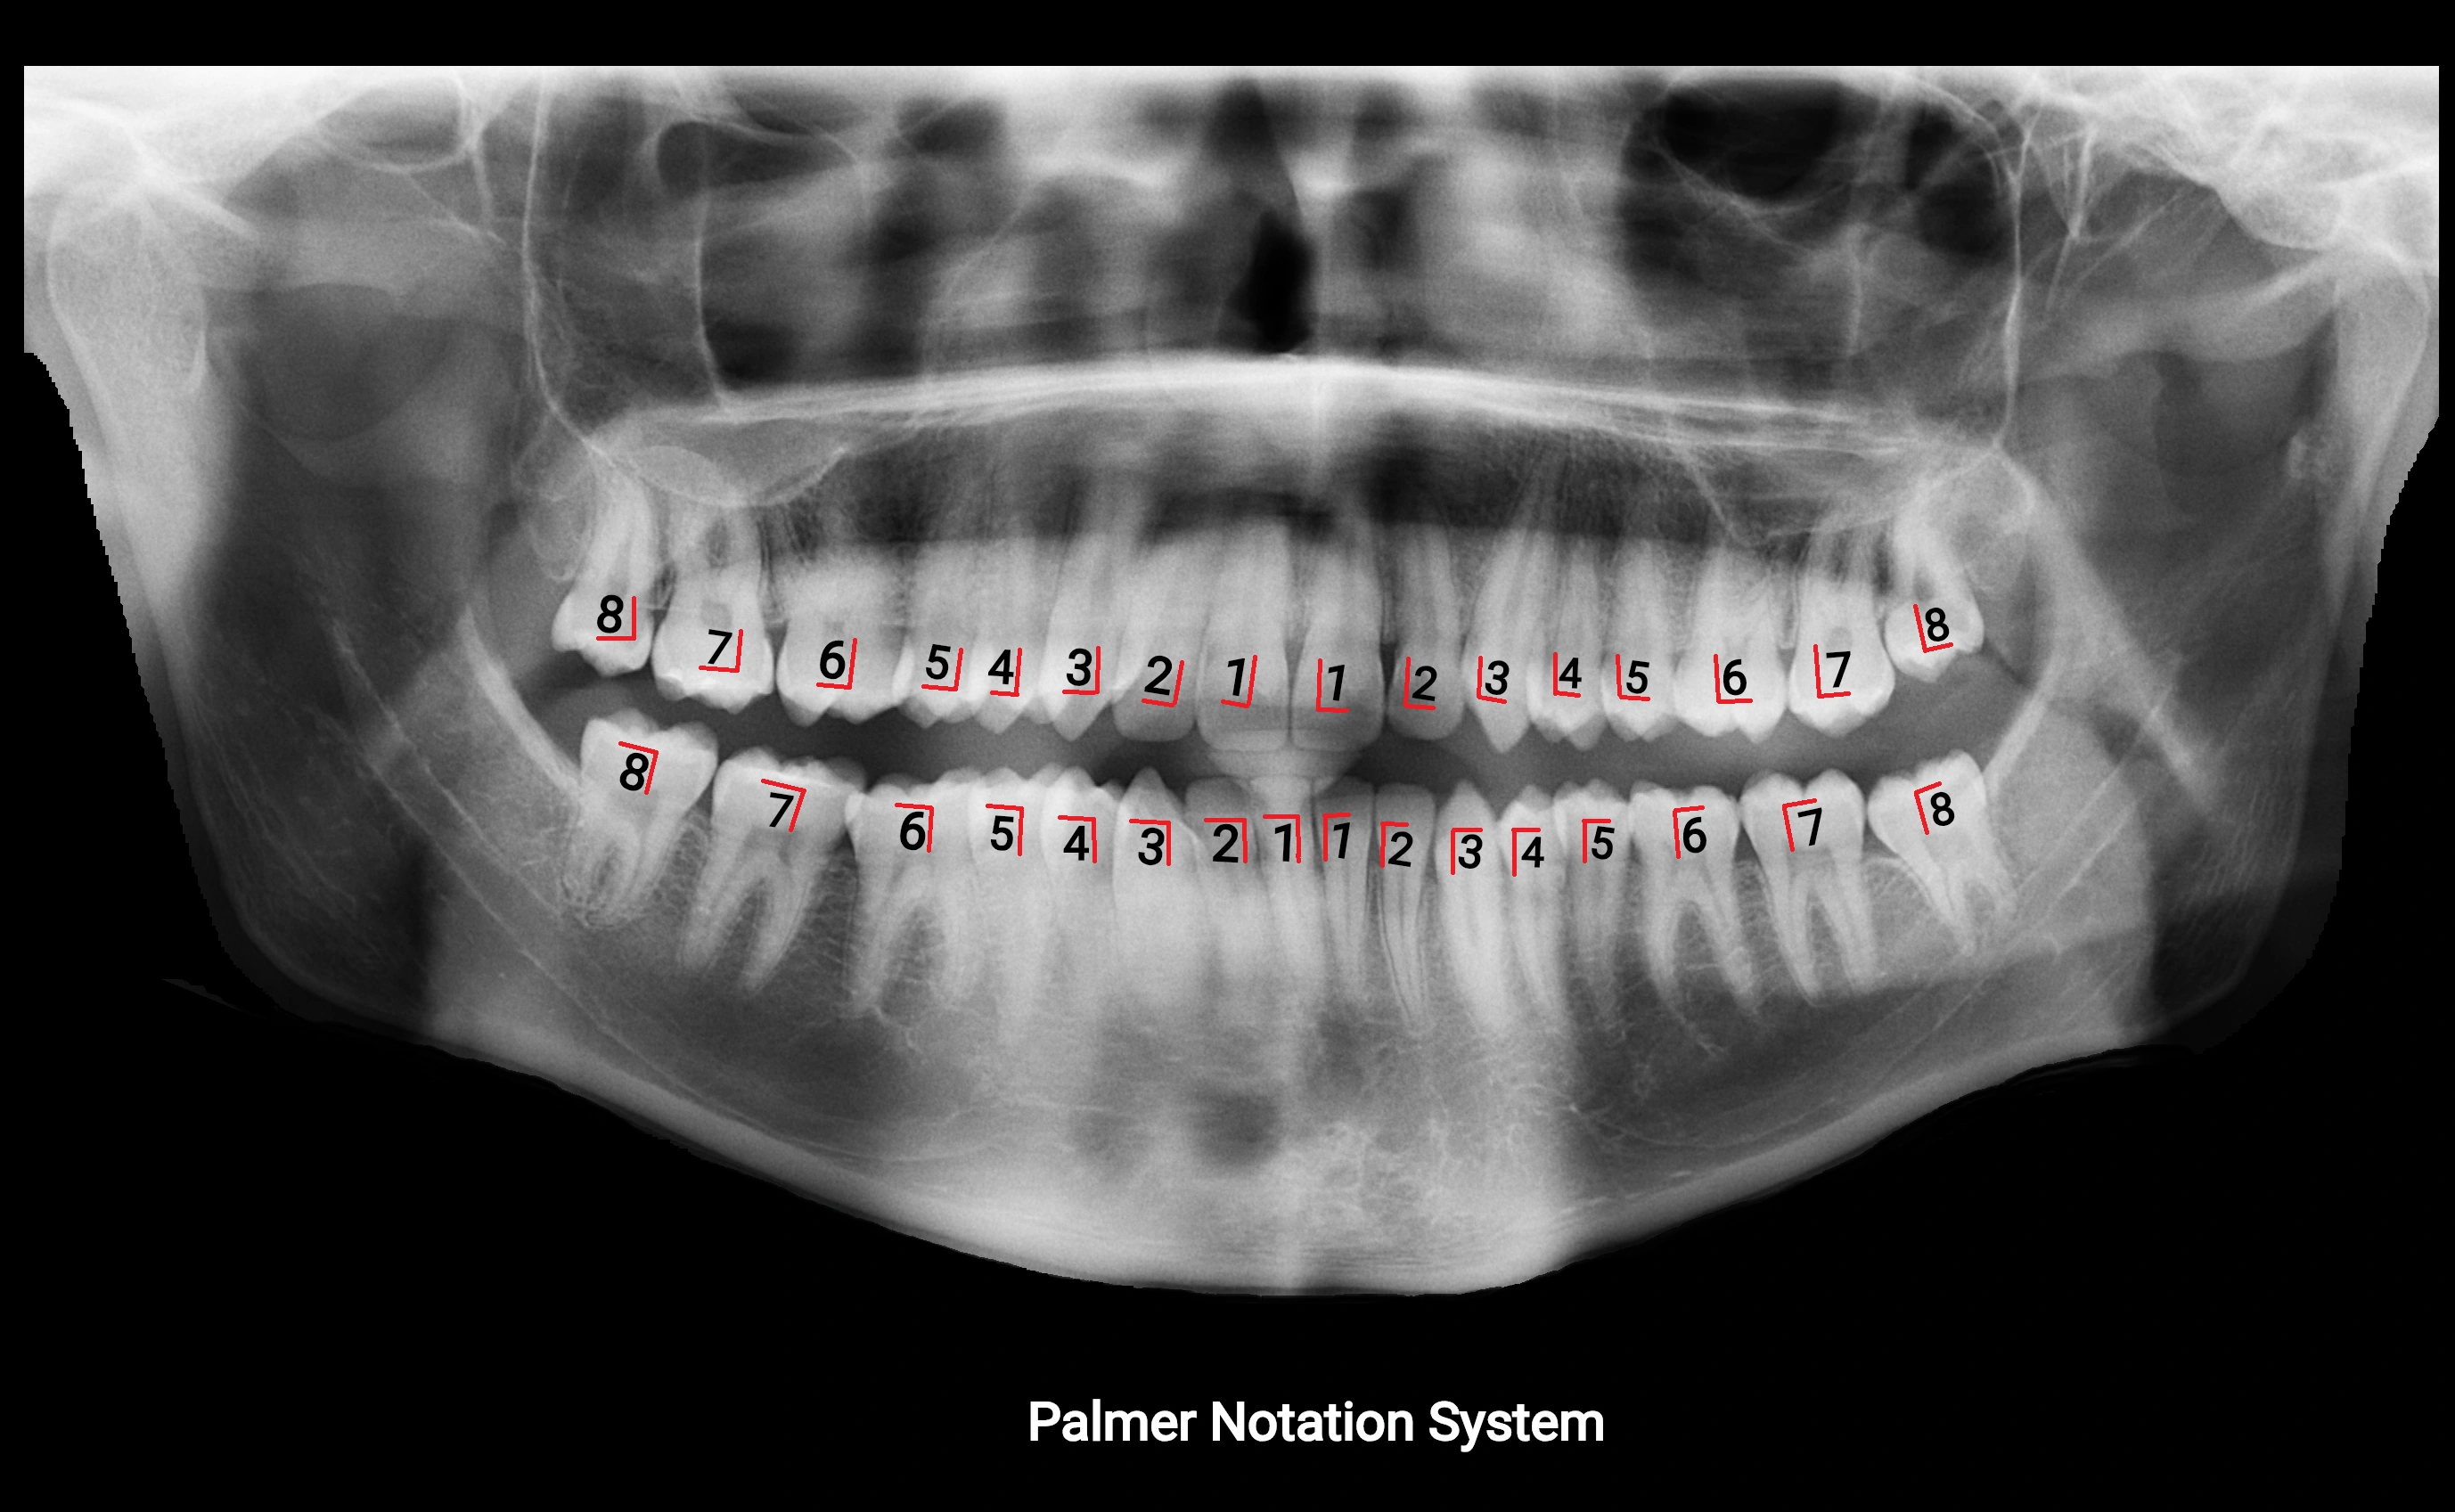

The alveolar process of the maxilla is the bony ridge of the maxilla that houses the upper teeth, extending from the anterior nasal spine to the maxillary tuberosity posteriorly. It consists of compact cortical bone on its outer surfaces and trabecular (cancellous) bone internally, with alveolar sockets (dental alveoli) forming individualized cavities for each tooth. The alveolar process develops in association with tooth eruption and resorption, adapting its shape and volume throughout life. It also forms part of the hard palate medially and contributes to the architecture of the midface, supporting the upper lip, cheeks, and nasal floor.